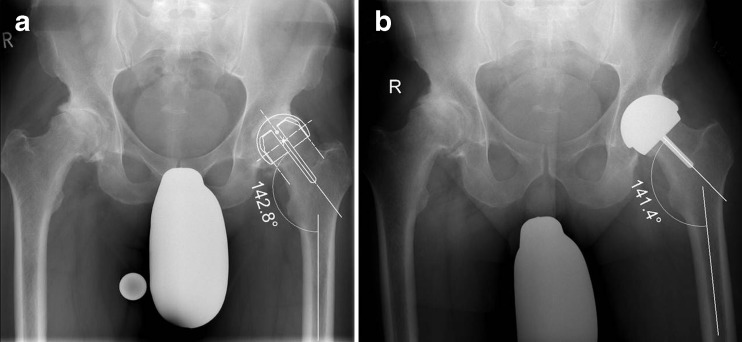

SSA was defined as the angle between the stem of the femoral HR component and the axis of the femoral diaphysis in the AP projection. Non-optimal femoral component positioning as the primary end point of the study was defined as five degrees or more absolute, e.g. either relative varus or valgus, deviation from the planned SSA as illustrated in Fig. 5. Additionally, relative varus deviation from the planned SSA, superolateral head/neck offset, femoral offset, femoral length, mediolateral femoral neck diameter, cup inclination, heterotopic ossifications classified according to Brooker et al. [18] and radiological signs of femoral neck notching and bone/implant impingement were assessed on post-operative and six month AP films, respectively.

Fig. 5.

Planned SSA (a) and post-operative SSA (b) as determined on a standardised AP projection